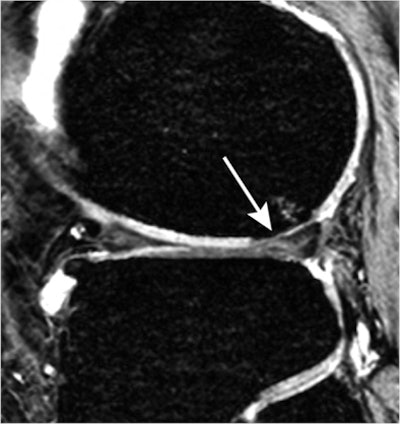

| Sagittal 3D gradient-echo MR image shows cartilaginous defect (arrow) and bone marrow lesion in lateral femoral condyle in a 54-year-old woman with ACL rupture and meniscal tears 10 years ago. The sequence was used to score the cartilage lesions. Fat-suppressed fast spin-echo sequence was used to score the bone marrow lesion. The ACL rupture was not reconstructed, and the medial meniscal tear was treated with partial meniscectomy. Image courtesy of Radiology. |

In the analysis of MR images, the researchers found that patients with anterior cruciate ligament (ACL) ruptures had an increased risk of developing joint space narrowing, cartilaginous defects, osteophytes, bone marrow lesions, and subchondral cysts medially or laterally.

In conclusion, the authors wrote that "irrespective of treatment, the risk factors seen on knee MR images resulted in localized development of osteoarthritis 10 years later."

The different patterns of developing osteoarthritis are determined according to the initial ACL and meniscal injuries, they also noted. "The hallmark finding of osteoarthritis development after medial meniscal tears is diffuse medial cartilage loss, and after lateral meniscal tears, it is focal lateral cartilage loss. After ACL rupture, osteoarthritis characteristics are seen medially and laterally," they wrote.